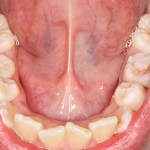

А еще через неделю мы планировали снимать швы, но они отвалились сами собой:

Как видите, от кисты и проведенной операции даже следа не осталось: